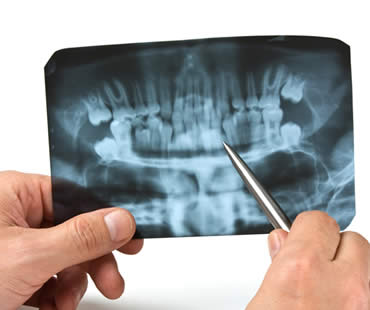

Wisdom teeth got their name because they are the final teeth to develop, usually in the late teens to early twenties, at a time when a person becomes fully mature or “wise.” Wisdom teeth are the third and final set of molars in the very back of the mouth. Most people...